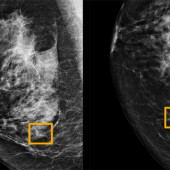

Artificial intelligence improves breast cancer detection on mammograms in early research

A new Artificial Intelligence model detects and predicts breast cancer in mammography scans more accurately than radiologists, reducing false positives and false negatives.